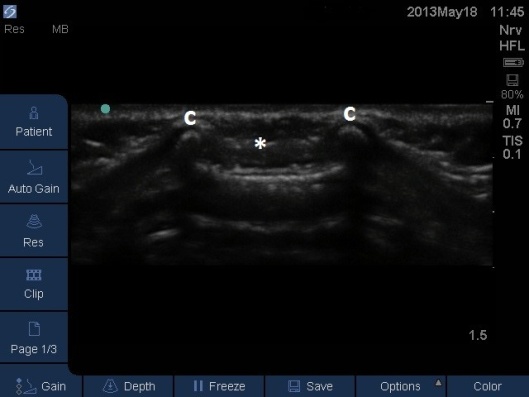

Fig 3. Ultrasound Probe in Midline Transverse position moved cephalad along sacrum.

C – sacral cornu, white asterisk sacrococcygeal membrane.

- Prior to performing the caudal a ‘Mapping’ or ‘Scout’ scan is performed to assess the position of the dural sac in relation to the sacrococcygeal membrane. The angle of needle/cannula insertion can be observed. See Figs 1-7.